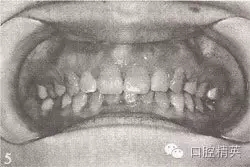

參見圖9-33 雙側后牙鎖頜矯治前后

A.雙側后牙鎖頜矯治前

B.雙側后牙鎖頜矯治后